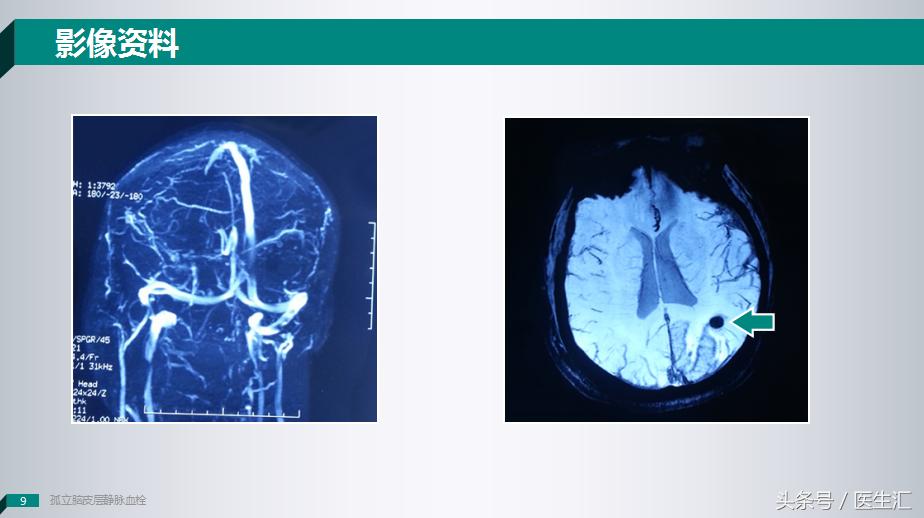

这个时候我们给患者做了一个SWI头颅磁敏感加权成像上提示这个病灶可能是一个出血的病变,但是我们给患者做MRV成像的时候却发现也没有什么问题。

因为这个患者贴近皮层,所以我们就给患者做了一个DSA的检查,我们可以看到这个患者患侧的大脑上静脉是有的,但是枕叶静脉是明显缺失的。

所以说这个时候我们应该可以确诊了,这个病人是一个少见的:皮层静脉血栓。